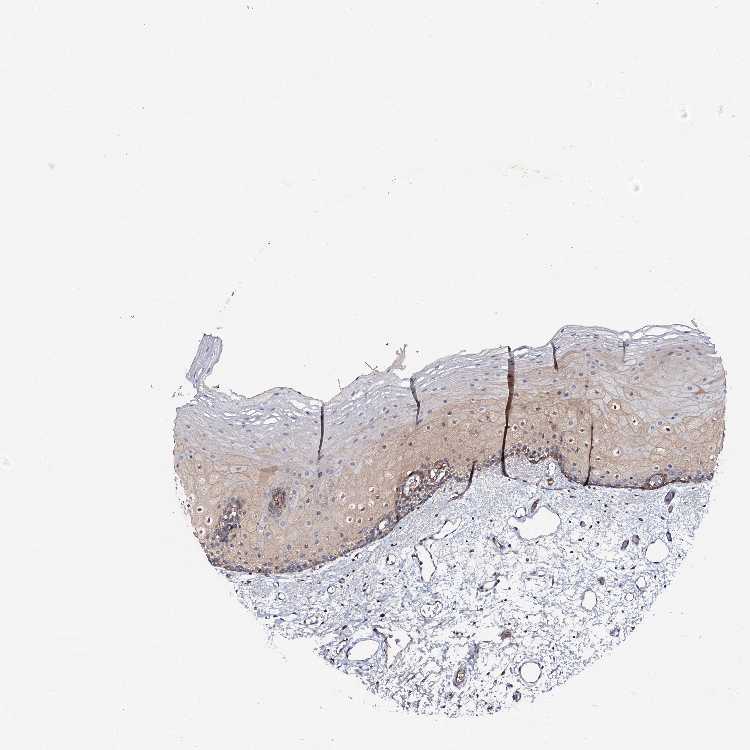

TISSUE PRIMARY DATA ORAL MUCOSA Show tissue menu

ORAL MUCOSA - Antibody stainingi

Antibody staining in the annotated cell types in the current human tissue is reported as not detected, low, medium, or high, based on conventional immunohistochemistry profiling in selected tissues. This score is based on the combination of the staining intensity and fraction of stained cells.

Each image is clickable and will lead to virtual microscopy that enables deeper exploration of all samples and also displays staining intensity scores, fraction scores and subcellular localization as well as patient and tissue information for each sample.

Antibody HPA020873Antibody HPA040413

Squamous epithelial cells MediumMedium